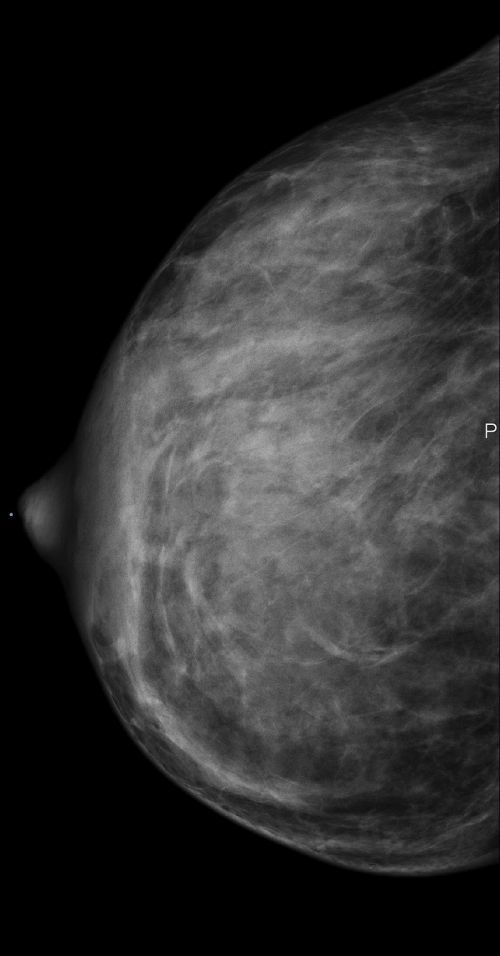

ACR-Klassifikation der Brustdichte in der Mammographie

Die ACR-Klassifikation der Brustdichte in der Mammographie ist ein System zur Einteilung der Brustgewebe in vier Kategorien, die von A bis D reichen. In Deutschland wird der anstatt ACR der Begriff Beurteilbarkeitsstufe verwendet.

Die Kategorie A steht für eine fast vollständig fettreiche Brust, die Kategorie B für eine überwiegend fettreiche Brust mit einigen fibroglandulären Bereichen, die Kategorie C für eine heterogen dichte Brust mit mehreren fibroglandulären Bereichen und die Kategorie D für eine extrem dichte Brust mit sehr wenig Fettgewebe.

Die Brustdichte ist ein wichtiger Faktor für die Erkennung von Brustkrebs, da dichtes Gewebe die Beurteilbarkeit der Mammographie erschweren und mögliche Tumoren verdecken kann. Die ACR-Klassifikation der Brustdichte in der Mammographie hilft den Radiologen, die Aussagekraft der Mammographie zu beurteilen. Je dichter das Drüsengewebe, desto sinnvoller ist eine zusätzliche Methode wie Mamma-Sonographie oder Mamma-MRT.